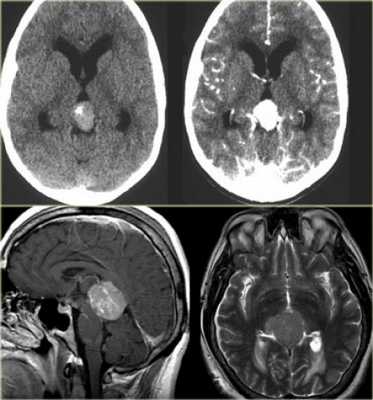

Опухоль пинеальной области головного мозга

К опухоли пинеальной области головного мозга относятся как к поражению железы шишковидной. Но нередко поражение возникает в средней части четверохолмия и задних отделах третьего желудочка. Здесь очень часто могут возникать такие поражения как карционома, гнерминома. Следует отметить, что пинеальные опухоли могут сочетаться с блоком ликовроциркуляции, что становится основой развития гидроцефалии.

Чаще всего при образовании в пинеальной области назначается его удаление. Операция может производиться при минимальном травматизме при помощи эндоскопического инструментария. Также используется процесс открытого типа (если размеры образования большие, устранение предполагает необходимость аккуратного отделения).

Лечение пинеальной опухоль головного мозга

Лечение назначается исходя из проведенных обследований. Обязательно при поражении пинеальной области берутся все лабораторные анализы и онкомаркеры, после чего назначается КТ и МРТ. Получив результаты обследования, врач может четко определить последовательность действий. Чаще всего требуется операция, причем удаление производится как можно быстрее. Пинеальная опухоль головного мозга может иметь достаточно большие размеры, что делает процесс лечения крайне затруднительным. Нередко просто нельзя удалять такое поражение из-за возможности нанести пациенту непоправимый вред.

Назначая лечение врач должен ориентироваться на общей клинической картине, использовать максимальный процесс диагностирования, оценить общее состояние пациента, определить возможность устранение образования без нанесения вреда. В случае, если традиционные методики терапии по мнению врача не дадут нужного результата следует прибегать к применению оперативного процесса в сочетании с химиотерапией, медикаментозными препаратами, радиотерапией и пр.

Прогноз жизни

Опухоль пинеальной области головного мозга может быть доброкачественной, если она диагностируется на ранней стадии, а лечение является комплексным и оперативным, то есть вероятность вернуть пациента к нормальной жизни.

Если же опухоль пинеальной области головного мозга злокачественная, то в данном случае лечение должно включать в себя удаление, воздействие химиотерапией, радиоизлучением и пр. На ранних стадиях лечение дает позитивные результаты, но рецидив возможен в 20-25% случаев. Если же образование имеет большие размеры и последнюю стадию развития, то даже после удаления возможен рецидив в 30-45%, а в некоторых случаях невозможно делать операцию.